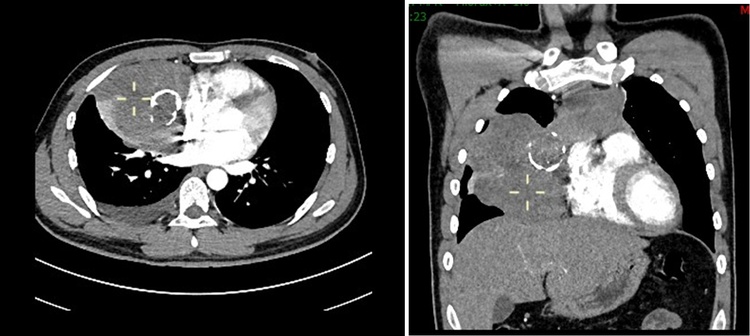

莫先生今年27岁,近年来在行走后经常出现下肢无力的情况,尤其是爬楼梯后更感觉迈不动腿。近3月来,症状逐渐加重并出现眼皮下垂、视物重影、咀嚼无力、发音不清、活动后胸闷、气促、咳嗽及胸痛等症状,且症状晨轻暮重。小莫意识到自己身体出现了状况,在家人的陪同下来到深圳市中医院检查。CT检查发现前上纵隔有一巨大肿块,直径达10cm。肿块向右侧胸腔生长且与上腔静脉、无名静脉、心包及右肺中叶分界不清(图1)。经脑病心理科和心胸外科联合会诊,诊断为胸腺瘤合并全身型重症肌无力。由于肿瘤巨大,已经压迫或侵犯邻近心脏、血管和肺组织,且胸腺肿瘤伴随有重症肌无力表现,莫先生面临随时出现呼吸循环衰竭的可能,疾病严重威胁着他的生命。

图1:CT扫描提示胸腺巨大肿瘤,凸向右侧胸腔生长,右侧胸腔积液。